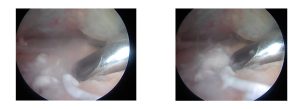

Barbotaj ve diğer yöntemlerin yetersiz kaldığı durumlarda, omuz artroskopisi ile cerrahi müdahale yapılabilir.